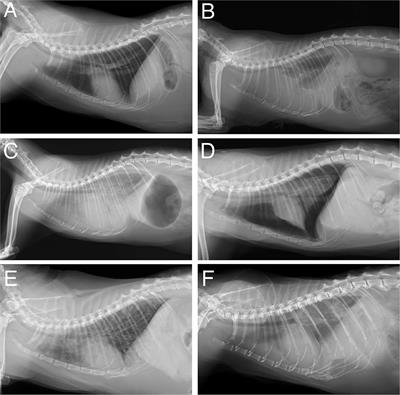

Frontiers An Ai Based Algorithm For The Automatic Classification Of Thoracic Radiographs In Cats Veterinary Science